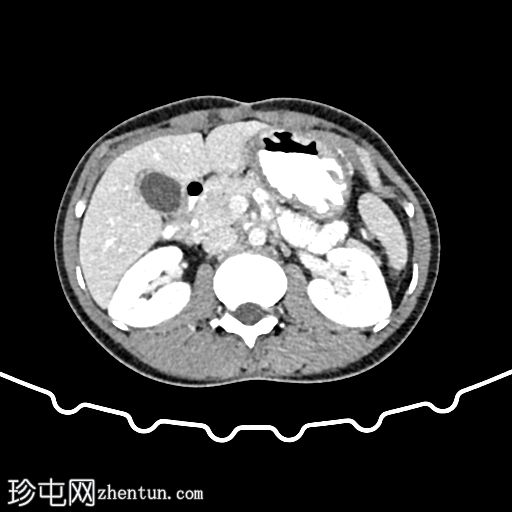

轴位增强扫描(门静脉期)

肝外胆管、肝内胆管及胆囊内可见气体。后续增强(静脉)检查中加用口服造影剂,结果显示造影剂从十二指肠反流至胆总管,最终进入胆囊。